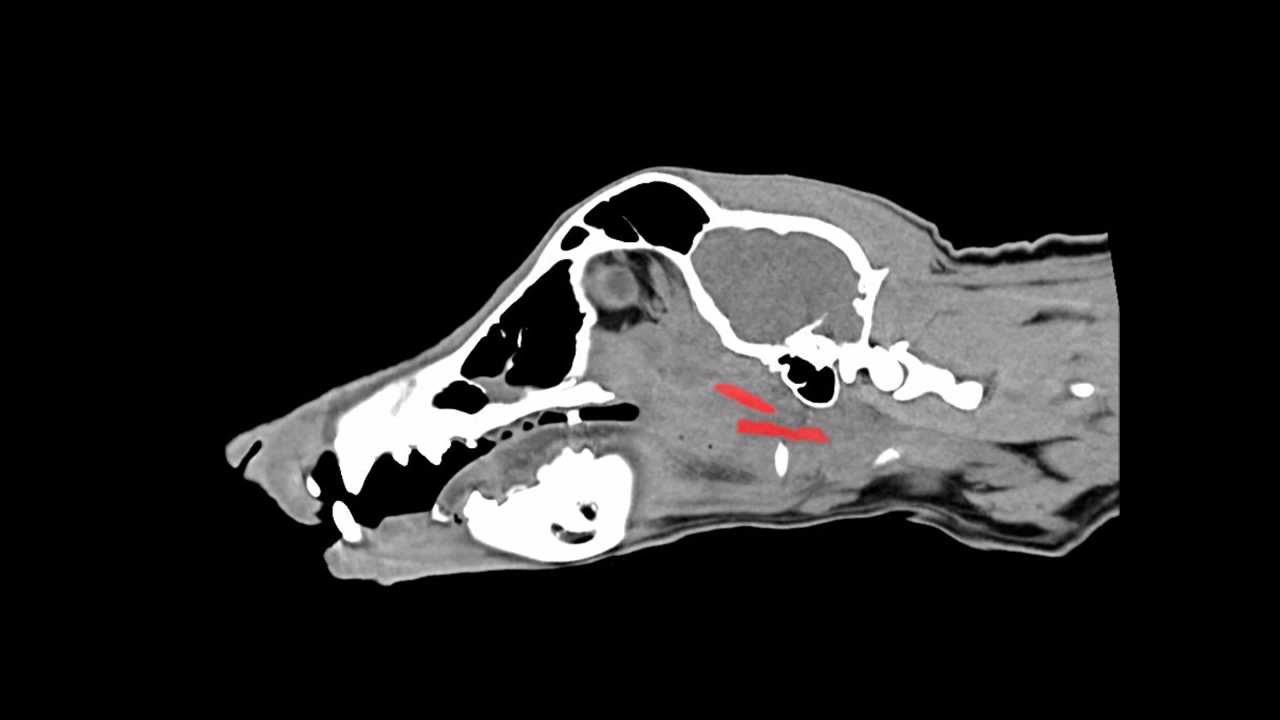

CT-SCAN

Date | 12-06-2022 | Radiologist | Name of radiologist |

Description Lorem Ipsum is simply dummy text of the printing and typesetting industry. Lorem Ipsum has been the industry's stan |

Observation Lorem Ipsum is simply dummy text of the printing and typesetting industry. Lorem Ipsum has been the industry's stan |